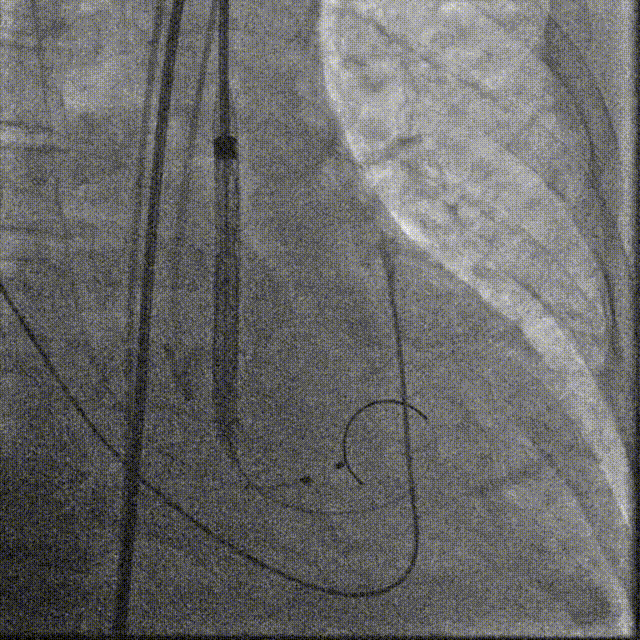

TaurusElite AV29号瓣膜定位及释放。瓣膜初始定位-3位,开花后120次起搏,释放到工作位后造影显示锚定充足,位置良好,冠脉未见遮挡,继续缓慢旋转手柄,轻推输送器,瓣膜逐一脱钩,顺利释放。

瓣膜初始定位

瓣膜释放过程

TaurusElite AV26瓣膜轻松过弓跨瓣,瓣膜初始定位瓣环0位,120bpm起搏下精准释放,释放到工作位后造影显示锚定充足,位置良好,冠脉未见遮挡,继续完成释放。